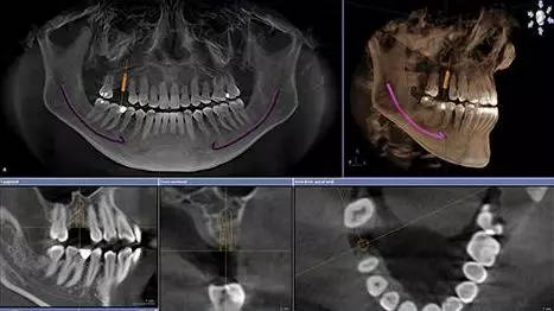

拍片检查。

一般拔牙3个月后,牙槽骨吸收趋于稳定,即可到医院进行拍片和口内检查。

种植前需要拍全景片、颌骨CT、验血等检查,不同的口腔情况所需的种植术式复杂程度不同,对口腔的健康程度也有一定的要求,部分情况还需提前设计种植导板。时间大概需要数天。